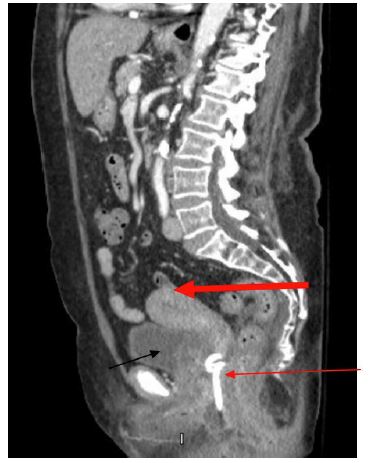

On post-operative day (POD) 9, the patient presented with fever and vulvar pain. Her exam revealed induration along left labia extending lateral to the anus. Computer tomography (CT) showed an abscess (Figure 1). Patient underwent incision and drainage and drain placement in the operating room. After 48 hrs of intravenous Piperacillin/Tazobactam she was discharged home with oral Amoxicillin/Clavulanic acid to complete a 14-day course.

Figure 1: POD 9 – Pelvic CT shows 7 x 4.3 x 5.2 cm lower pelvic/perineal abscess (thin red arrow) with fluid-filled uterus (thick red arrow) consistent with pyometra. Bladder shown with a thin black arrow.